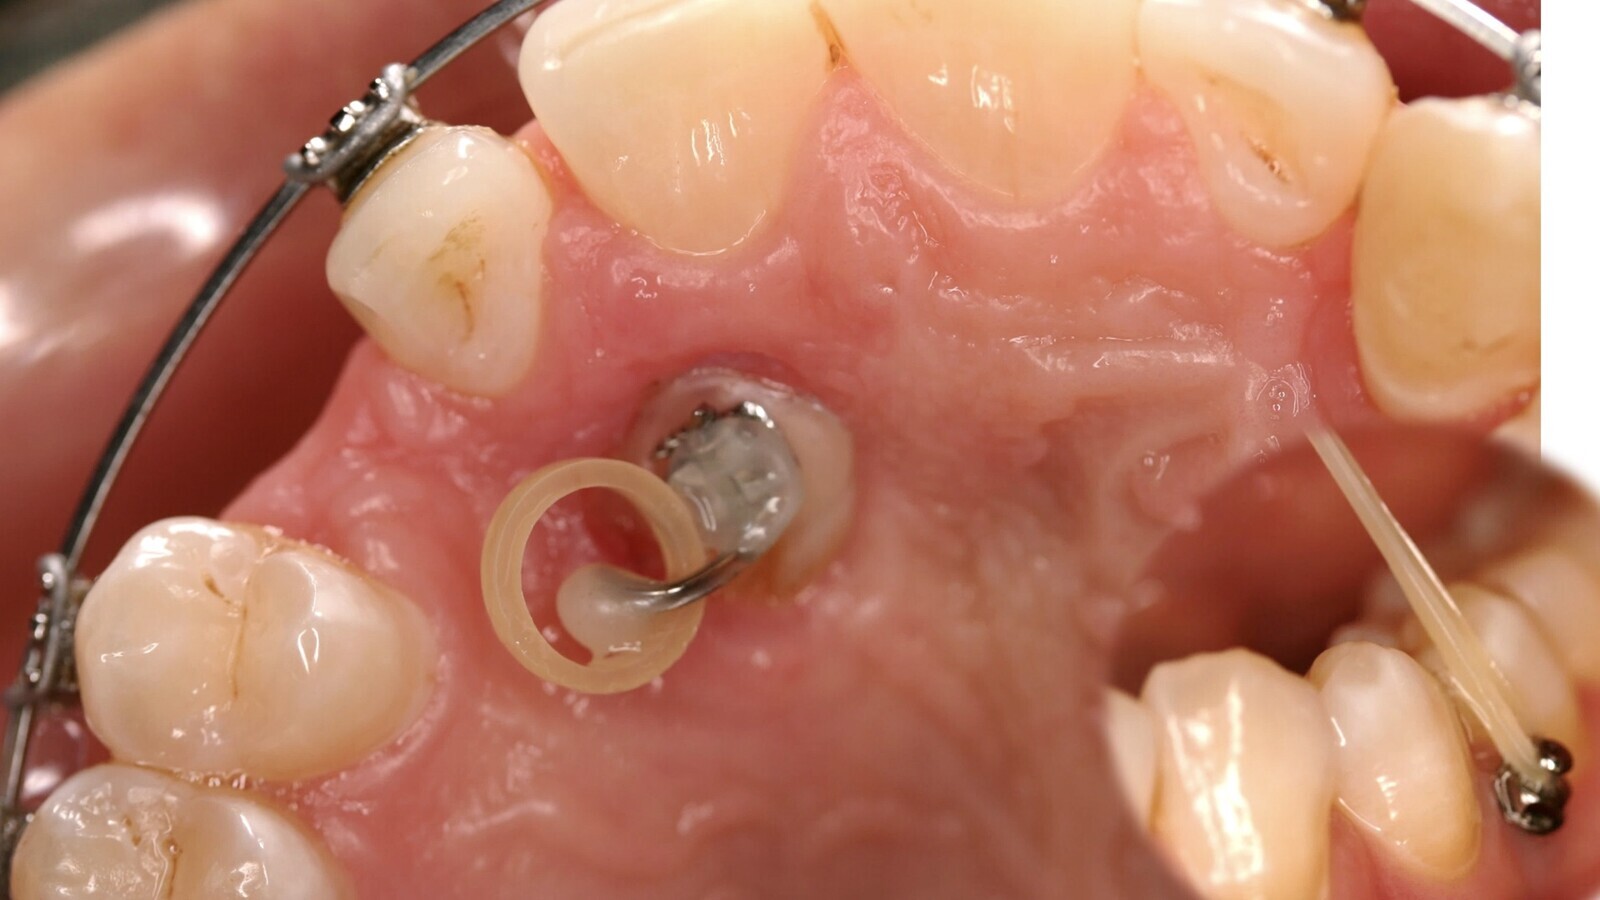

9. En nuestra experiencia, las Microosteoperforaciones en el hueso enfrentado al movimiento dentario es una excelente opción para acelerar el movimiento dentario ortodóncico y acortar la duración del tratamiento. Estas Microosteoperforaciones, realizadas con una fresa de tugsteno a 2-4-7 mm de profundidad estimulan el RAP (rapid acelerated phenomen) y el reclutamiento de células progenitoras y osteoclastos (figuras 19 y 20).

Figuras 19 y 20. Las Microosteoperforaciones en el hueso enfrentado al movimiento dentario son una excelente opción para acelerar el movimiento dentario ortodóncico y acortar la duración del tratamiento.